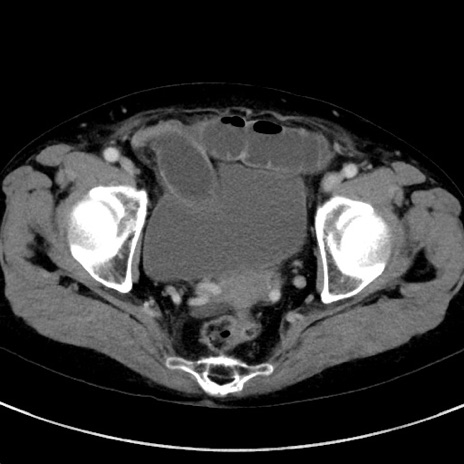

症例23(横断像)

【症例】70歳代女性

【主訴】下腹部痛・嘔吐

【現病歴】2日前より腹痛あり。昨日嘔吐あり。症状改善しないため来院。

【既往歴】胃GISTに対して胃部分切除後。

【身体所見】BT 37.1℃、BP 128/77mmHg、腹部:平坦・軟、下腹部に圧痛あり。

【データ】WBC 10200、CRP 0.31